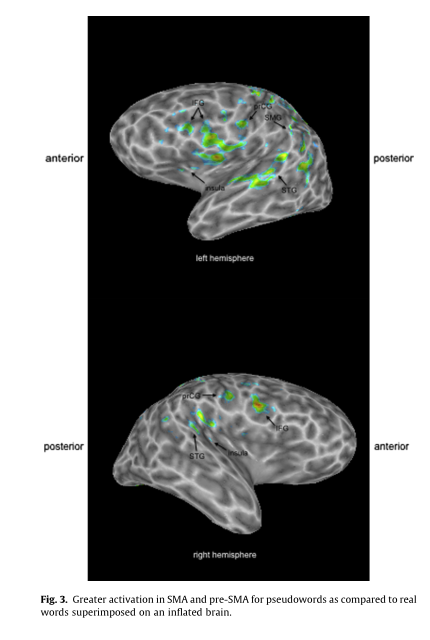

在本研究中,参与者接受功能性磁共振成像,并重复长度,复杂性和初始音节频率相似的真词和假词。与真实单词相比,假单词的产生在许多言语生产网络中产生了更大的激活,包括双侧额下叶皮层、中央前回和补充运动区,以及左侧颞上皮层和前岛叶。只有右中额回对真实词语的激活强于假词语。与无语音控制条件相比,产生假词或真实词会激活构成语音产生网络的所有区域。我们的数据与之前的研究相结合,表明被确定为语音产生的基本单位受到所研究语音的性质的影响,即,真实单词与其他真实单词的比较,伪单词与其他伪单词的比较,或真实单词与伪单词的比较。

与真词相比,假词的产生在负责语音生成的大脑区域显示出更大的激活,包括在执行更高要求的语音任务时的激活区域。具体见图1。